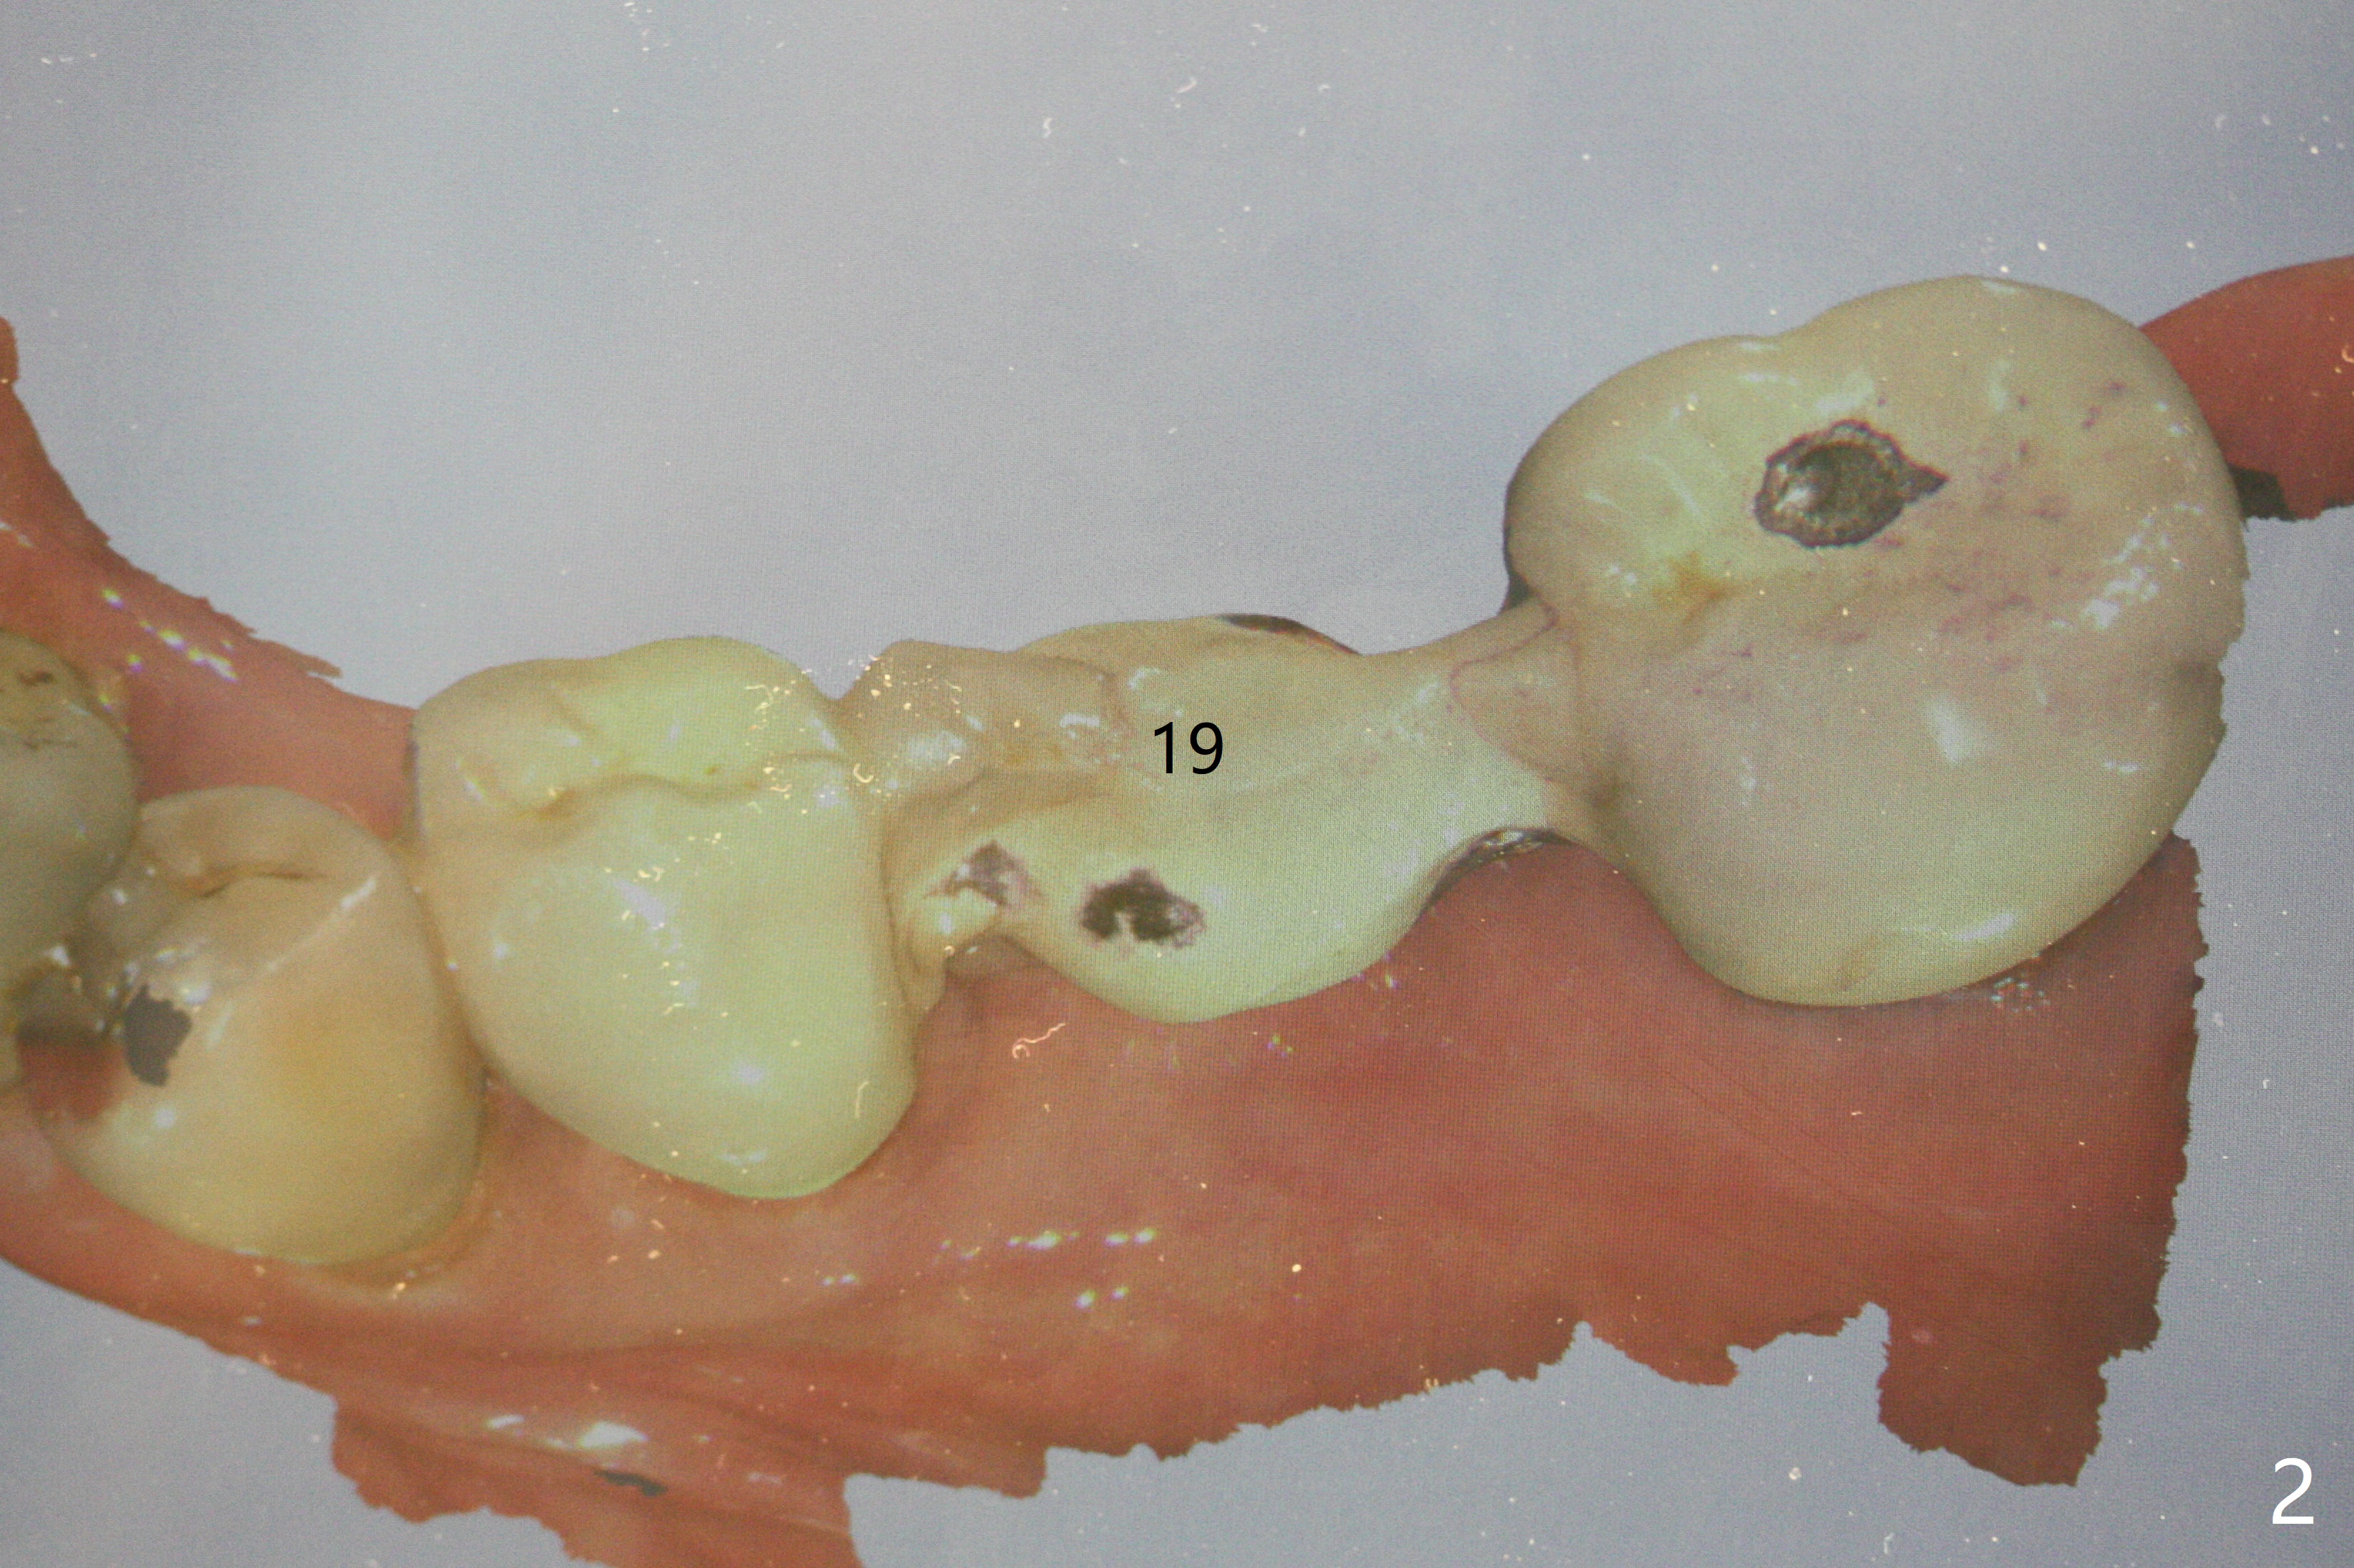

A 62-year-old man with sign of bruxism (#19 porcelain chip (Fig.2), 28 fracture/extraction) complains of severe mastication pain at #15 (Fig.1). More severe pain is elicited when the buccal cusps bite on a bite stick than the palatal one (Fig.3 with suspicious crazing lines). CT shows bone loss around the palatal root (Fig.4 P). A 5x11.5 mm implant will be placed immediately (Fig.5). The bone at #28 is able to hold a 3.5x13 mm implant (Fig.6). It is extremely difficult to take photos for 2nd molar crack line with a regular camera (Fig.3). The Shining Oral Scanner acts additionally as an intraoral camera. As a busy clinician, I do not have time to take photos for #19 porcelain chip. My assistants take over the task. After work, I am able to have bumper harvest. With the information just mentioned, I will be in a better position to present a more comprehensive treatment plan to the patient when treatment at #15 is finished: remove #18-20 bridge, place an implant at #19 and fabricate new crowns at #18 and 20.